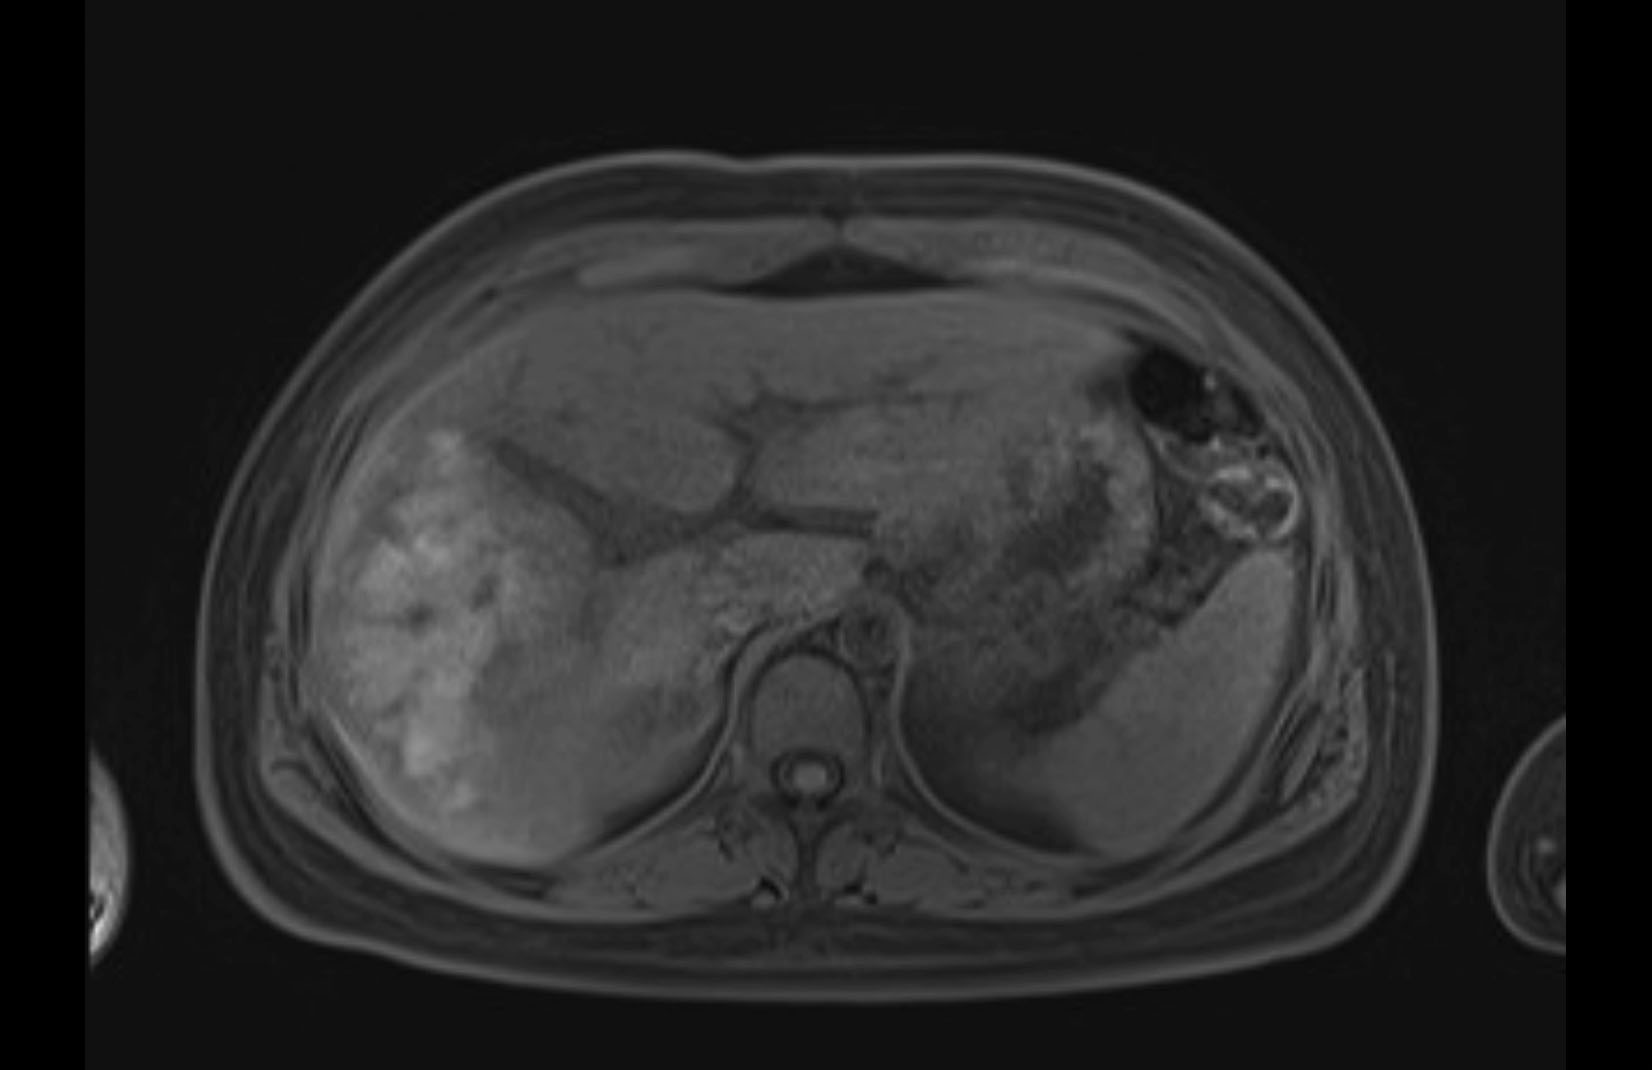

Imaging Analysis

Look through the patient's CT scan to identify any areas of concern for the necessary procedure.

MRI T1

Based on initial findings, which issue(s) would you be most concerned about?